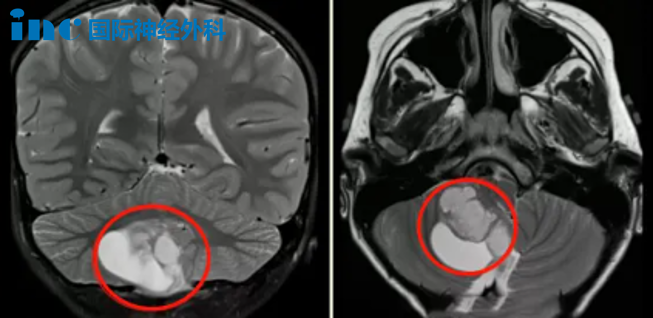

尽管此时的肿瘤已经达到40mm*37mm大小,且四脑室、脑干受压,中线结构局部左移,但辰辰并未表现出其他症状。要尽早手术吗?如果能安全切除肿瘤,辰辰父母也许不会如此纠结,偏偏肿瘤生长在小脑-脑干位置,不仅切除难度大,而且术后很可能会出现瘫痪、昏迷等并发症。

巴教授:“MR 显示非常典型的小脑良性肿瘤,常见的是毛细胞性星形细胞瘤。患儿需要手术。完全切除肿瘤后,这个患儿几乎可以从肿瘤中康复。切除率必须达到 100%,我将尽一切努力实现这一重要目标。”

“从我们到达德国之后,一直到小孩进手术室,我心里对巴教授的信任基本是百分比的。”最终,辰辰的手术十分成功,肿瘤得到全切,脑干充分减压,对中脑的挤压/移位压力明显减少,小脑也复位了。术后病理结果为毛细胞型星形细胞瘤,WHO 1级,这代表着只要全切,辰辰的预后将很好,甚至有望达到长期生存的治愈性结局。